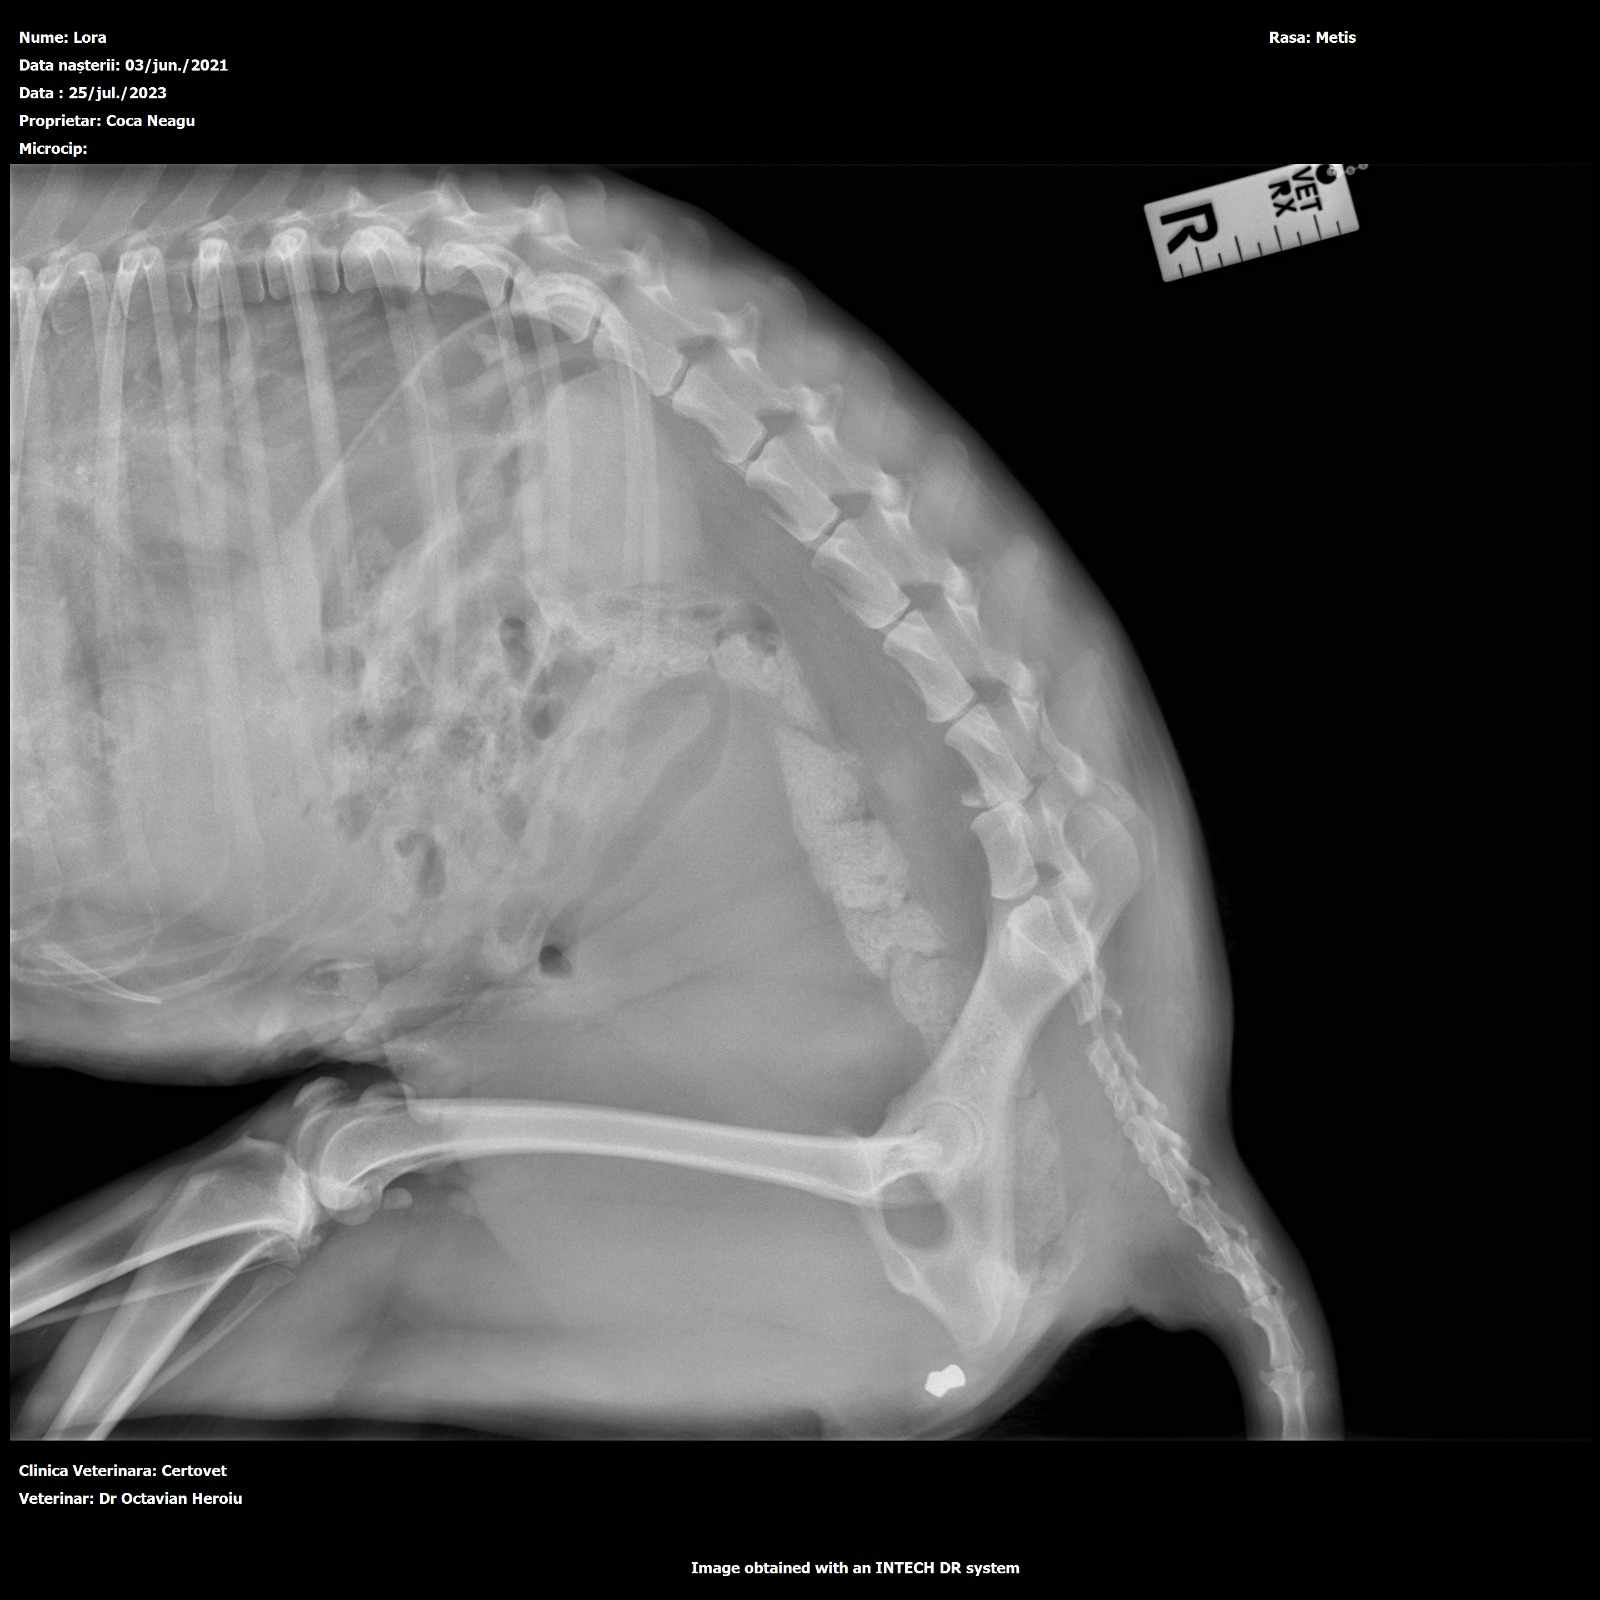

Gefunden wurde er im Sommer 2023 mit einem Pfeil in seinem Rücken, irgendeine abartige Kreatur hat versucht, den wehrlosen jungen Straßenhund zu töten!! (siehe Bilder)

Die Ärzte, die ihm den Pfeil rausoperierten, prognostizierten, dass er nie wieder würde laufen können, zu nah steckte der Pfeil an der Wirbelsäule…doch dann das Wunder: mithilfe von tollen Spendern konnten nicht nur die Kosten der OP sondern auch für einen Rolli gestemmt werden.